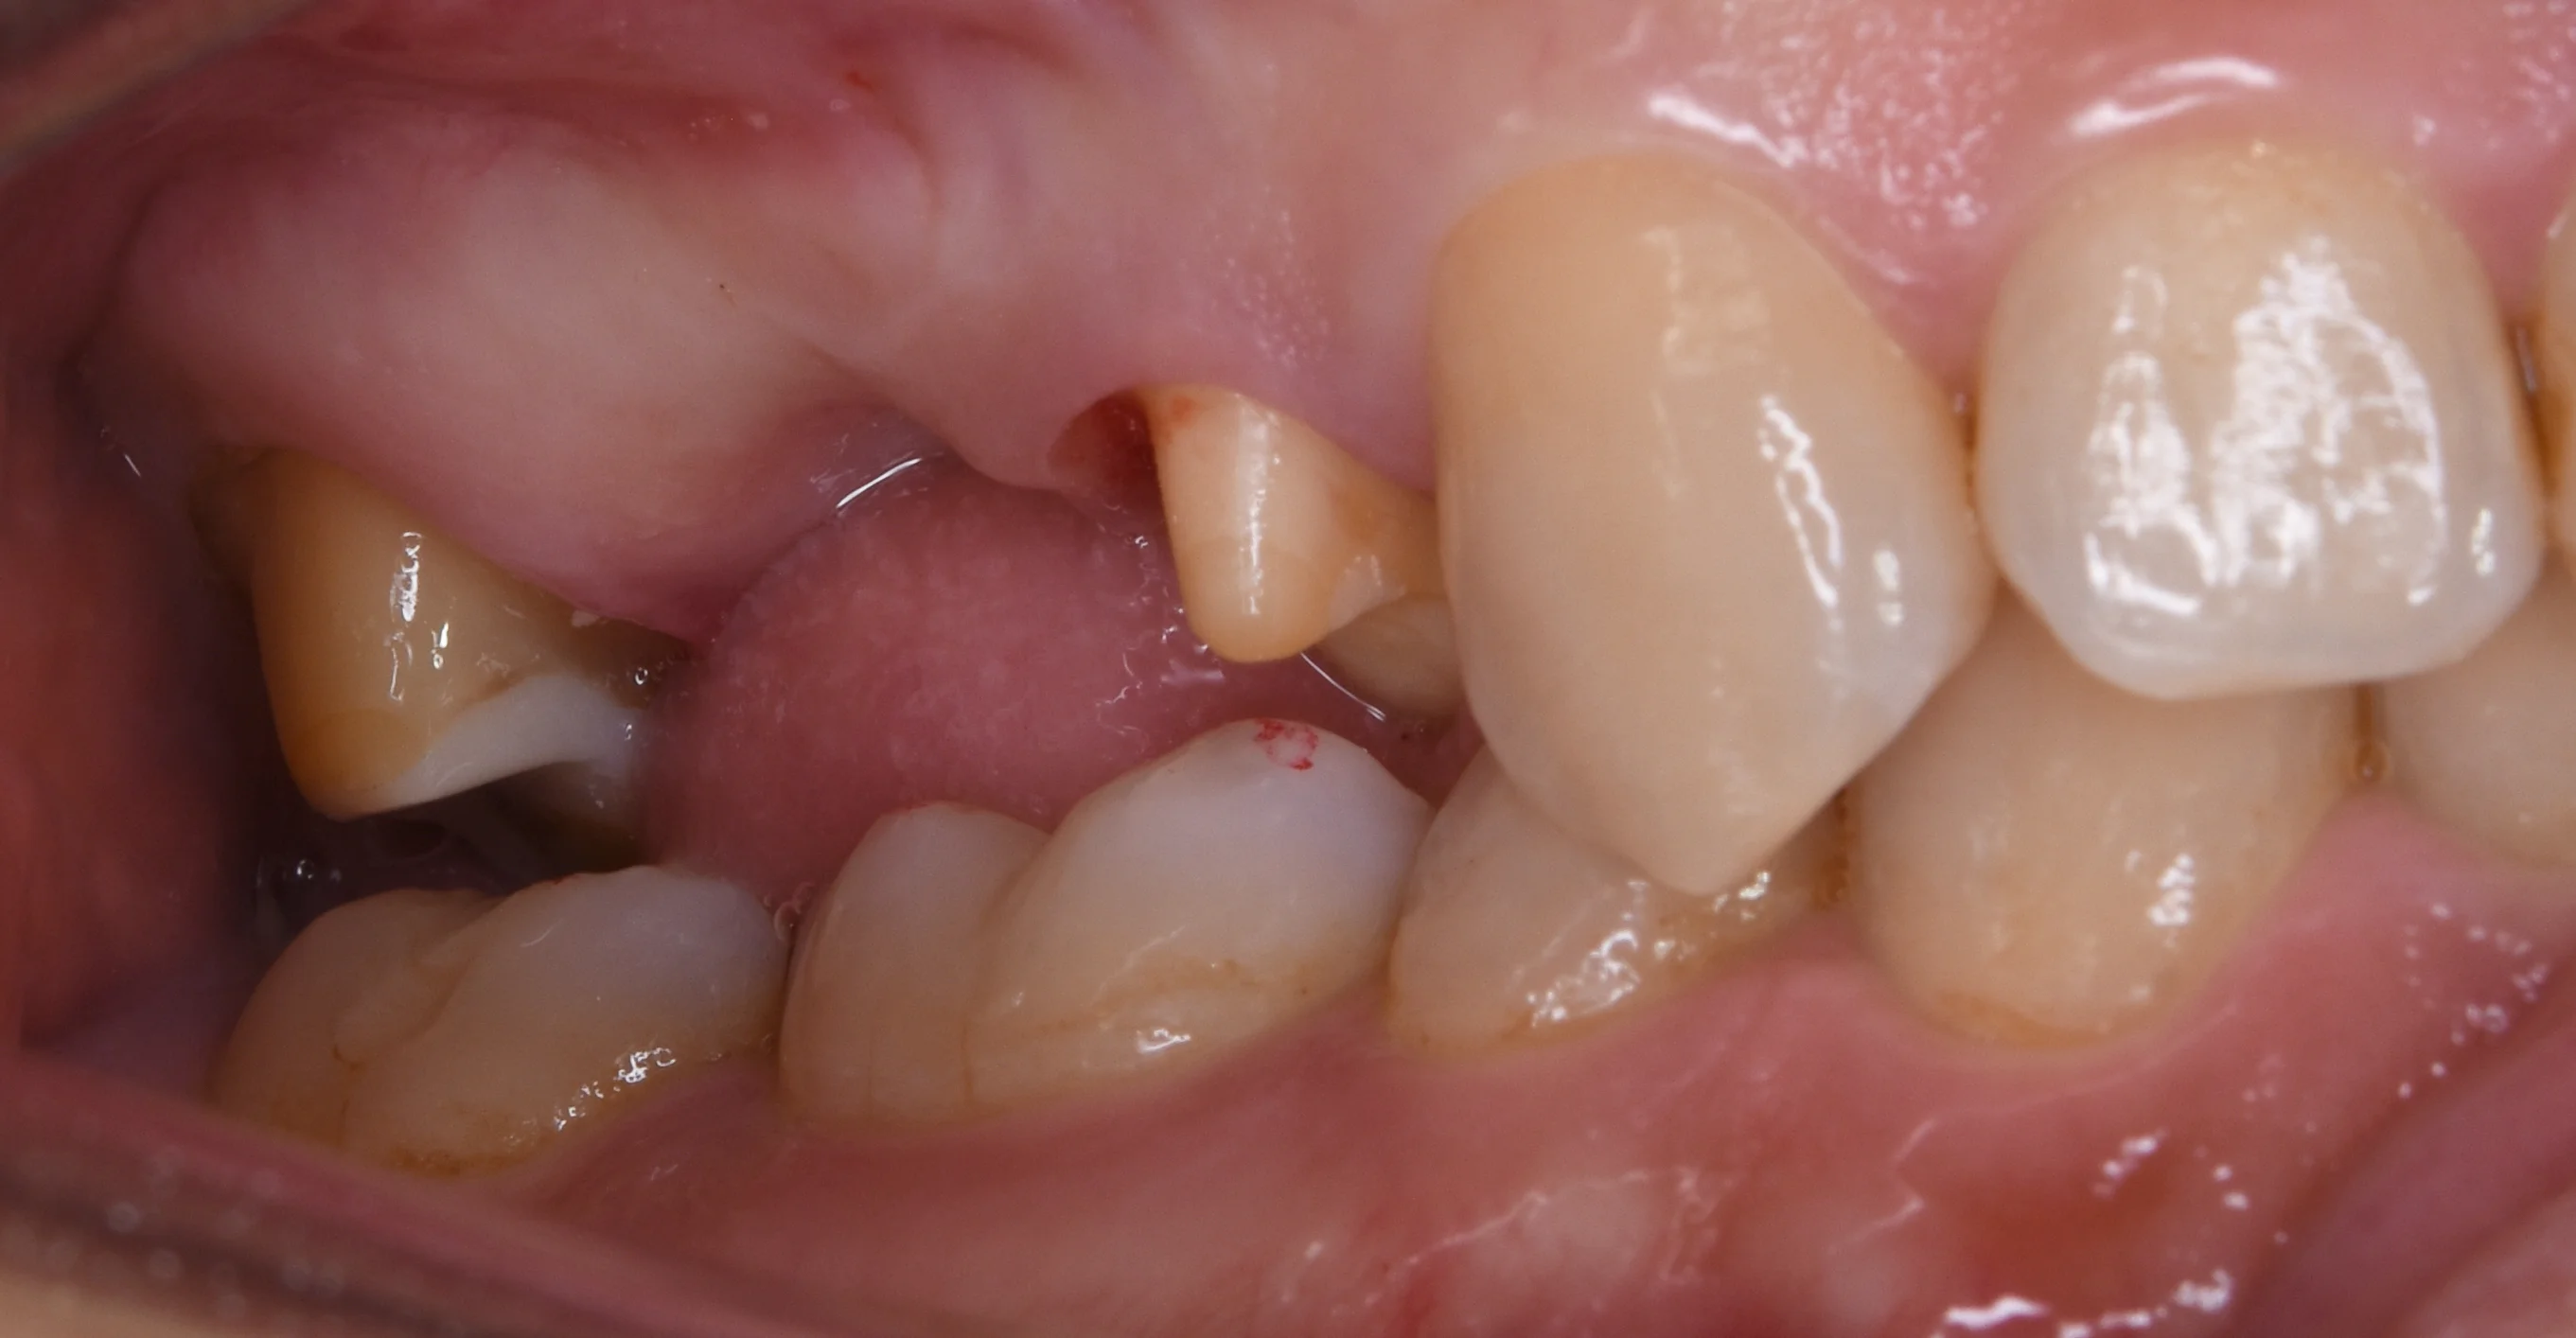

そしてSet時の写真です。

セラミックのブリッジ|坂寄歯科医院(取手市藤代) - 画像2

色調も形態も完璧ですね。

技工士さんが非常に上手く作ってくれていつも助かってます。

患者さんも歯ブラシを頑張ってくれているおかげで綺麗な歯茎の状態で入れることができましたね。

基本的なことですが、虫歯の治療にしても、被せ物を入れるにしても、歯茎の状態が綺麗じゃないと良い治療ができません。

歯周病があると歯茎に炎症があり、綺麗じゃなくなります。